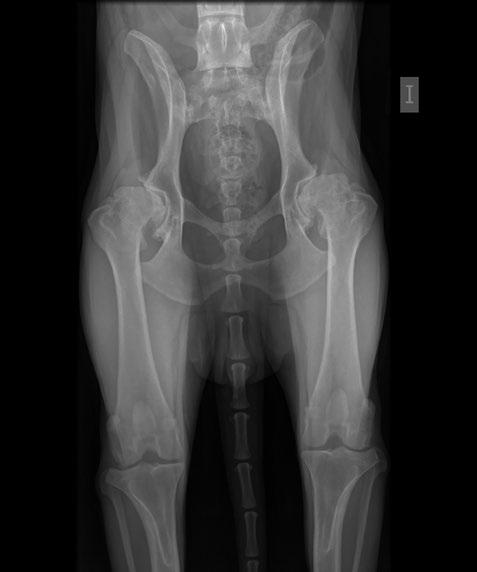

Radiografía en posición DAR para evaluar el borde acetabular dorsal con las mediciones realizas.

Radiografía en distracción de un perro radiológicamente inmaduro.

Modelo anatómico de una pelvis canina en la que se representa la maniobra de distracción.

Detalle de una radiografía ventrodorsal de cadera en un animal al que se le ha realizado la técnica de sinfisiodesis.

Los fémures se colocan perpendiculares a la mesa y con las rodillas en flexión. En esta posición, y con cierta presión hacia la mesa, los fémures se van abduciendo hasta que se nota un salto, que corresponde al punto en el que la cabeza del fémur vuelve a su • Vista en extensión: centro de la cabeza femoral medial al DAR. • Vista rana: congruencia articular. • Vista DAR: forma triangular, ángulo <6º. • Distracción: <0,4. Se considera que los perros han llegado a su grado máximo de distracción a las 14 semanas de edad.

Relación de la distancia entre el centro de la cabeza al centro del acetábulo y el radio de la cabeza.

Posteriormente, desde ese punto, se abduce el fémur de nuevo hasta percibir una traslación dorsolateral de la cabeza del fémur. Ese punto se puede medir y se conoce como ángulo de subluxación. • Estudio radiográfico: se deben realizar varias vistas, incluyendo ventrodorsal en extensión, compresión (rana) y vista del borde acetabular dorsal (DAR).